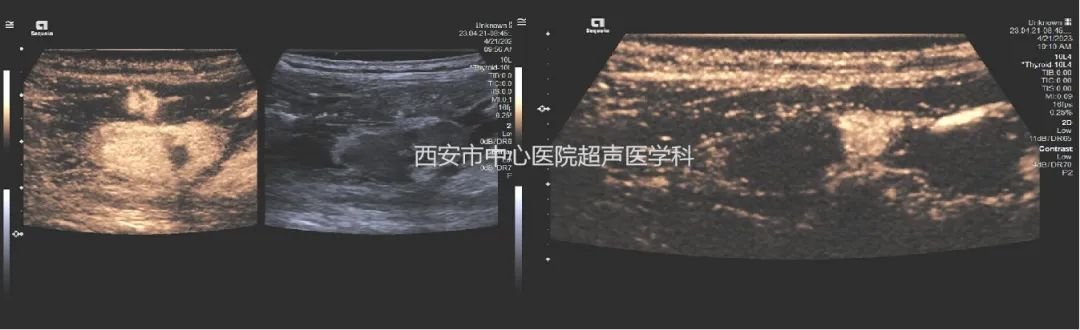

患者在得到诊断和可能引起的严重后果后非常紧张,可想到手术,又非常担心手术的风险及术后并发症,也不太接受手术后颈部的疤痕。权衡利弊,考虑到患者自身情况比较符合介入手术治疗,普外科便联系了超声医学科郑瑜主任,想利用热消融技术来代替传统手术,达到治疗效果,郑瑜主任通过二维及造影技术综合评估后,与临床医生商议了手术流程,充分术前谈话和风险告知,及时为患者进行了超声引导下甲状旁腺腺瘤的射频消融治疗。

局麻条件下,在超声实时监测下通过精细的液体注射隔离,将包块周围的神经、血管、甲状腺下极等完美的隔离保护起来,用细细的一根针进入腺瘤内,强回声的热气很快覆盖了腺瘤,一气呵成,仅仅不到10分钟便完成了整个手术,超声造影下血供丰富的高增强腺瘤结节完美的演变为无增强的“黑洞”,手术过程非常顺利,患者仅感到一点点灼热感,皮肤局部仅一个针眼,患者消融完便自行走回了病房。一天后,患者化验室检查数值回归正常水平,无其他不良反应。

超声引导下甲旁腺液体隔离及消融

术前高增强腺瘤,术后为充盈缺损